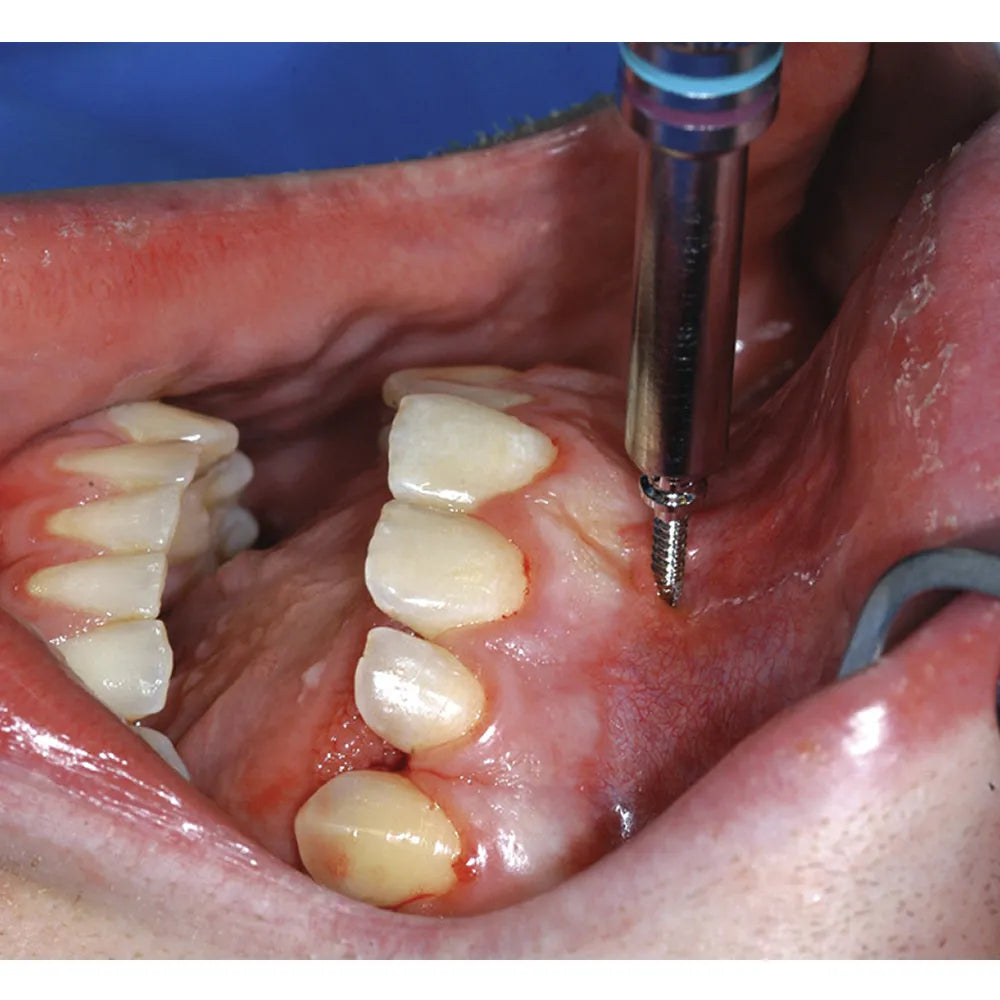

SK Surgicals SS IMF (Intermaxillary Fixation) Screws exemplify precision and reliability in maxillofacial surgery. Crafted from high-quality stainless steel, these screws are specifically designed for intermaxillary fixation, ensuring stability in cases of jaw fractures or surgical procedures requiring jaw immobilization. The self-drilling feature simplifies the insertion process, enhancing efficiency. Their versatile design accommodates various IMF techniques, and the compact size allows for minimally invasive applications. These screws facilitate quick and secure fixation, contributing to successful outcomes in maxillofacial procedures. With biocompatible materials and precise engineering, SK Surgicals SS IMF Screws are indispensable tools for oral and maxillofacial surgeons, providing essential support in achieving optimal patient outcomes.

- Self-Drilling Capability: Features a self-drilling mechanism, simplifying the insertion process and enhancing procedural efficiency.

SK Surgicals SS IMF (Intermaxillary Fixation) Screws exemplify precision and reliability in maxillofacial surgery. Crafted from high-quality stainless steel, these screws are specifically designed for intermaxillary fixation, ensuring stability in cases of jaw fractures or surgical procedures requiring jaw immobilization. The self-drilling feature simplifies the insertion process, enhancing efficiency. Their versatile design accommodates various IMF techniques, and the compact size allows for minimally invasive applications. These screws facilitate quick and secure fixation, contributing to successful outcomes in maxillofacial procedures. With biocompatible materials and precise engineering, SK Surgicals SS IMF Screws are indispensable tools for oral and maxillofacial surgeons, providing essential support in achieving optimal patient outcomes.

- Drilling (if required): If necessary, create a pilot hole using a suitable drill bit, considering the self-drilling capability of the screw.

- Screw Insertion: Using a screwdriver or appropriate instrumentation, carefully insert the IMF screw into the designated location.

- Controlled Tightening: Control the tightening process to achieve secure intermaxillary fixation without causing excessive trauma to surrounding tissues.